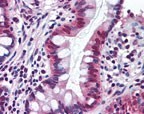

Supportive validation

- Submitted by

- OriGene (provider)

- Main image

- Experimental details

- Immunohistochemistry-Paraffin: SR1 Antibody [TA336980] - Analysis of human small intestine using this antibody at 10 ug/ml.

- Validation comment

- IHC